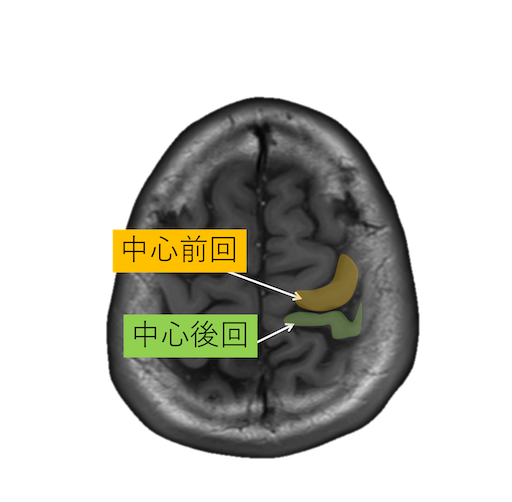

中心溝、中心前溝、中心後溝、中心前回、中心後回のMRI画像における解剖

主に脳梗塞診断などで重要な中心溝、中心前溝、中心後溝、中心前回、中心後回のMRI画像における解剖(CTでも使えます。)をご覧いただけます。

・脳回の前後幅は中心前回が後回より太い。